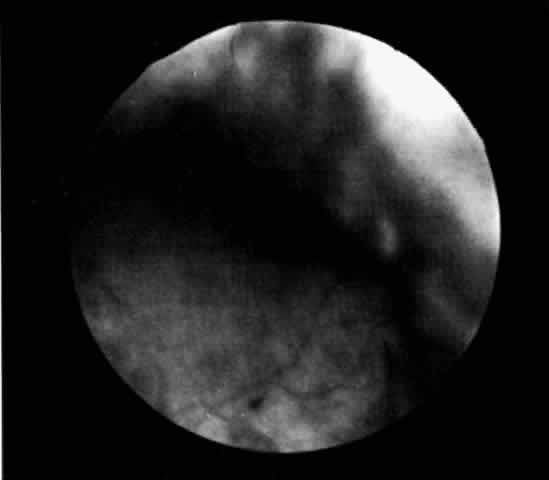

uveal process (Fig. 1). The effusion may extend under the pars plana, allowing visualization

of the ora serrata without scleral depression (Fig. 2).9 As shown in Figure 2, the surface of the elevation is convex and smooth, with a solid appearance

and a homogeneous grayish color. A shallow anterior chamber and

a low intraocular pressure may also suggest the diagnosis. Myopia in the

presence of anterior displacement of the lens-iris diaphragm may be

another diagnostic clue.10,11